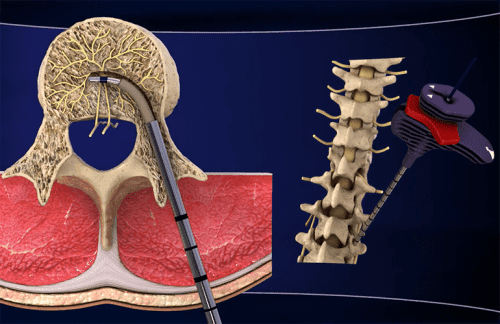

“INTRACEPT” هي إجراء جراحي لا يشبه عمليات العمود الفقري الجراحية التقليدية.

فالجراح أثناء هذه العملية يستخدم جهازًا صغيرًا لقتل العصب المسؤول عن آلام أسفل الظهر.

يستلقي المريض أولًا على وجهه لتلقي التخدير الموضعي في المنطقة الواقعة بين الفقرتين L3 و S1.

بعد ذلك، يتم إدخال إبرة دقيقة جدًا في هذه المنطقة لإيقاف نشاط العصب القاعدي. وذلك لأن العصب القاعدي يرسل إشارات الألم من العمود الفقري إلى الدماغ.

بذلك الإجراء السريع ومن خلال الجراحة الموضعية، يمكن تخفيف آلام أسفل الظهر.

يستخدم هذا العلاج طاقة ترددات راديوية. وهو ما يعني عدم استخدام الجراح للمشرط أثناء الجراحة التي لا تتسبب بأيّة جروح.

يرسل الجهاز طاقة الترددات الراديوية هذه ويشعر المريض بقليل من الحرارة فقط أثناء العملية.

يقوم الجراح بعد ذلك بإزالة الجهاز بسهولة ودون تعريض المريض لأية مضاعفات.

تستغرق العملية بأكملها في الواقع نحو الساعة، ويمكن للمريض أن يعود إلى المنزل مشيًا بعد الانتهاء مباشرةً.